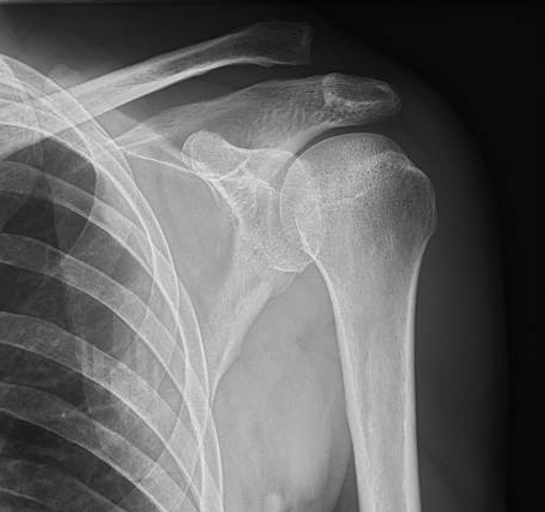

Rayos - X (Radiografía)

Las radiografías son un tipo de estudio de diagnóstico por imágenes que utiliza rayos X para penetrar el cuerpo y capturar imágenes de las estructuras internas. Los rayos X son absorbidos de manera diferente por los diferentes tejidos del cuerpo, lo que permite la creación de imágenes detalladas de huesos, órganos y tejidos blandos.